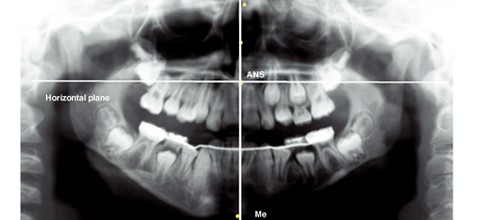

Die molare Achsenfehlstellung wurde wie folgt ermittelt: Auf jedem Orthopantomogramm wurden die Punkte Me (Menton, der am tiefsten gelegene Punkt am Rand der Mandibula, nahe der Symphyse), ANS (anterior nasal spine) und zwei willkürlich gewählte Punkte auf dem Nasenseptum lokalisiert und die Medialebene als Best-Fit-Verbindung dieser vier Punkte konstruiert. Danach wurde senkrecht zur Medialebene am ANS-Punkt (Abb. 7) eine weitere Linie, die sogenannte Horizontalebene, markiert. Durch Weiterverfolgen der Mittelpunkte der Okklusionsflächen erfolgte die Lokalisierung der Wurzeln jedes einzelnen Molaren. Die Verbindungslinie dieser beiden Punkte bildete die Längsachse des jeweiligen Molaren. Der am weitesten unten gelegene rechte Winkel zwischen Horizontalebene und Längsachse für die rechte Seite und der am weitesten unten gelegene linke Winkel für die linke Seite wurden zur Beschreibung der molaren Inklination verwendet (Abb. 7).

Abb. 7 Die Punkte Me, ANS, ND1 und ND2 (ND, nasal diaphragm) wurden zur Konstruktion einer Best-Fit-Linie verwendet, die als Medialebene genutzt wird. Eine vertikal zur Medialebene aufgesetzte Linie am ANS-Punkt diente als Horizontalebene.

Der Kronen- und Wurzelmittelpunkt jedes Molaren wurde lokalisiert und für die Konstruktion der Längsachse verwendet. Der untere rechte Winkel zwischen der Längsachse rechter Molaren auf der rechten Seite und der untere linke Winkel zwischen der Längsachse der linken Molaren und der Horizontalebene für die linke Seite wurde zur Beschreibung der Inklination verwendet.